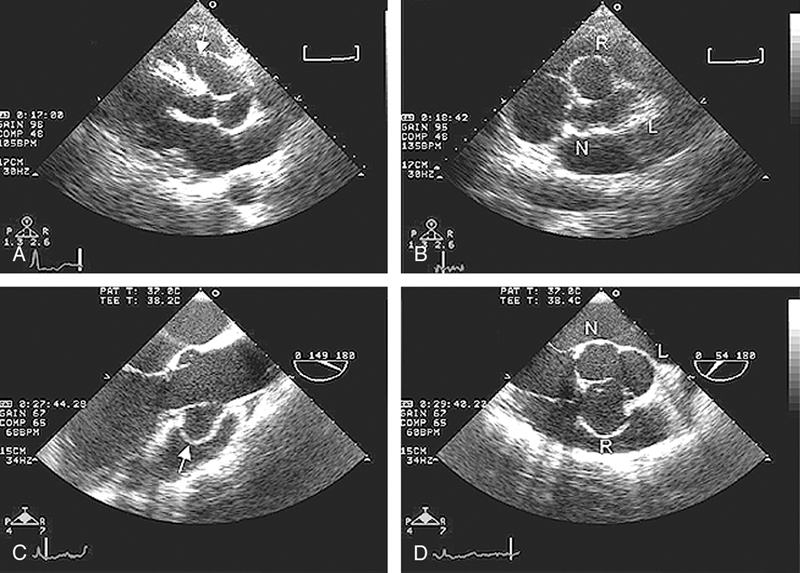

فحوصات تشخيصية لبعض امراض القلب والشرايين التاجية